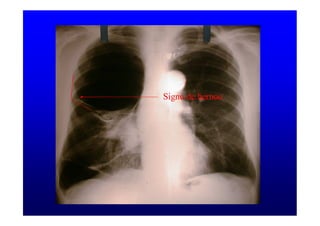

Signo de bernou